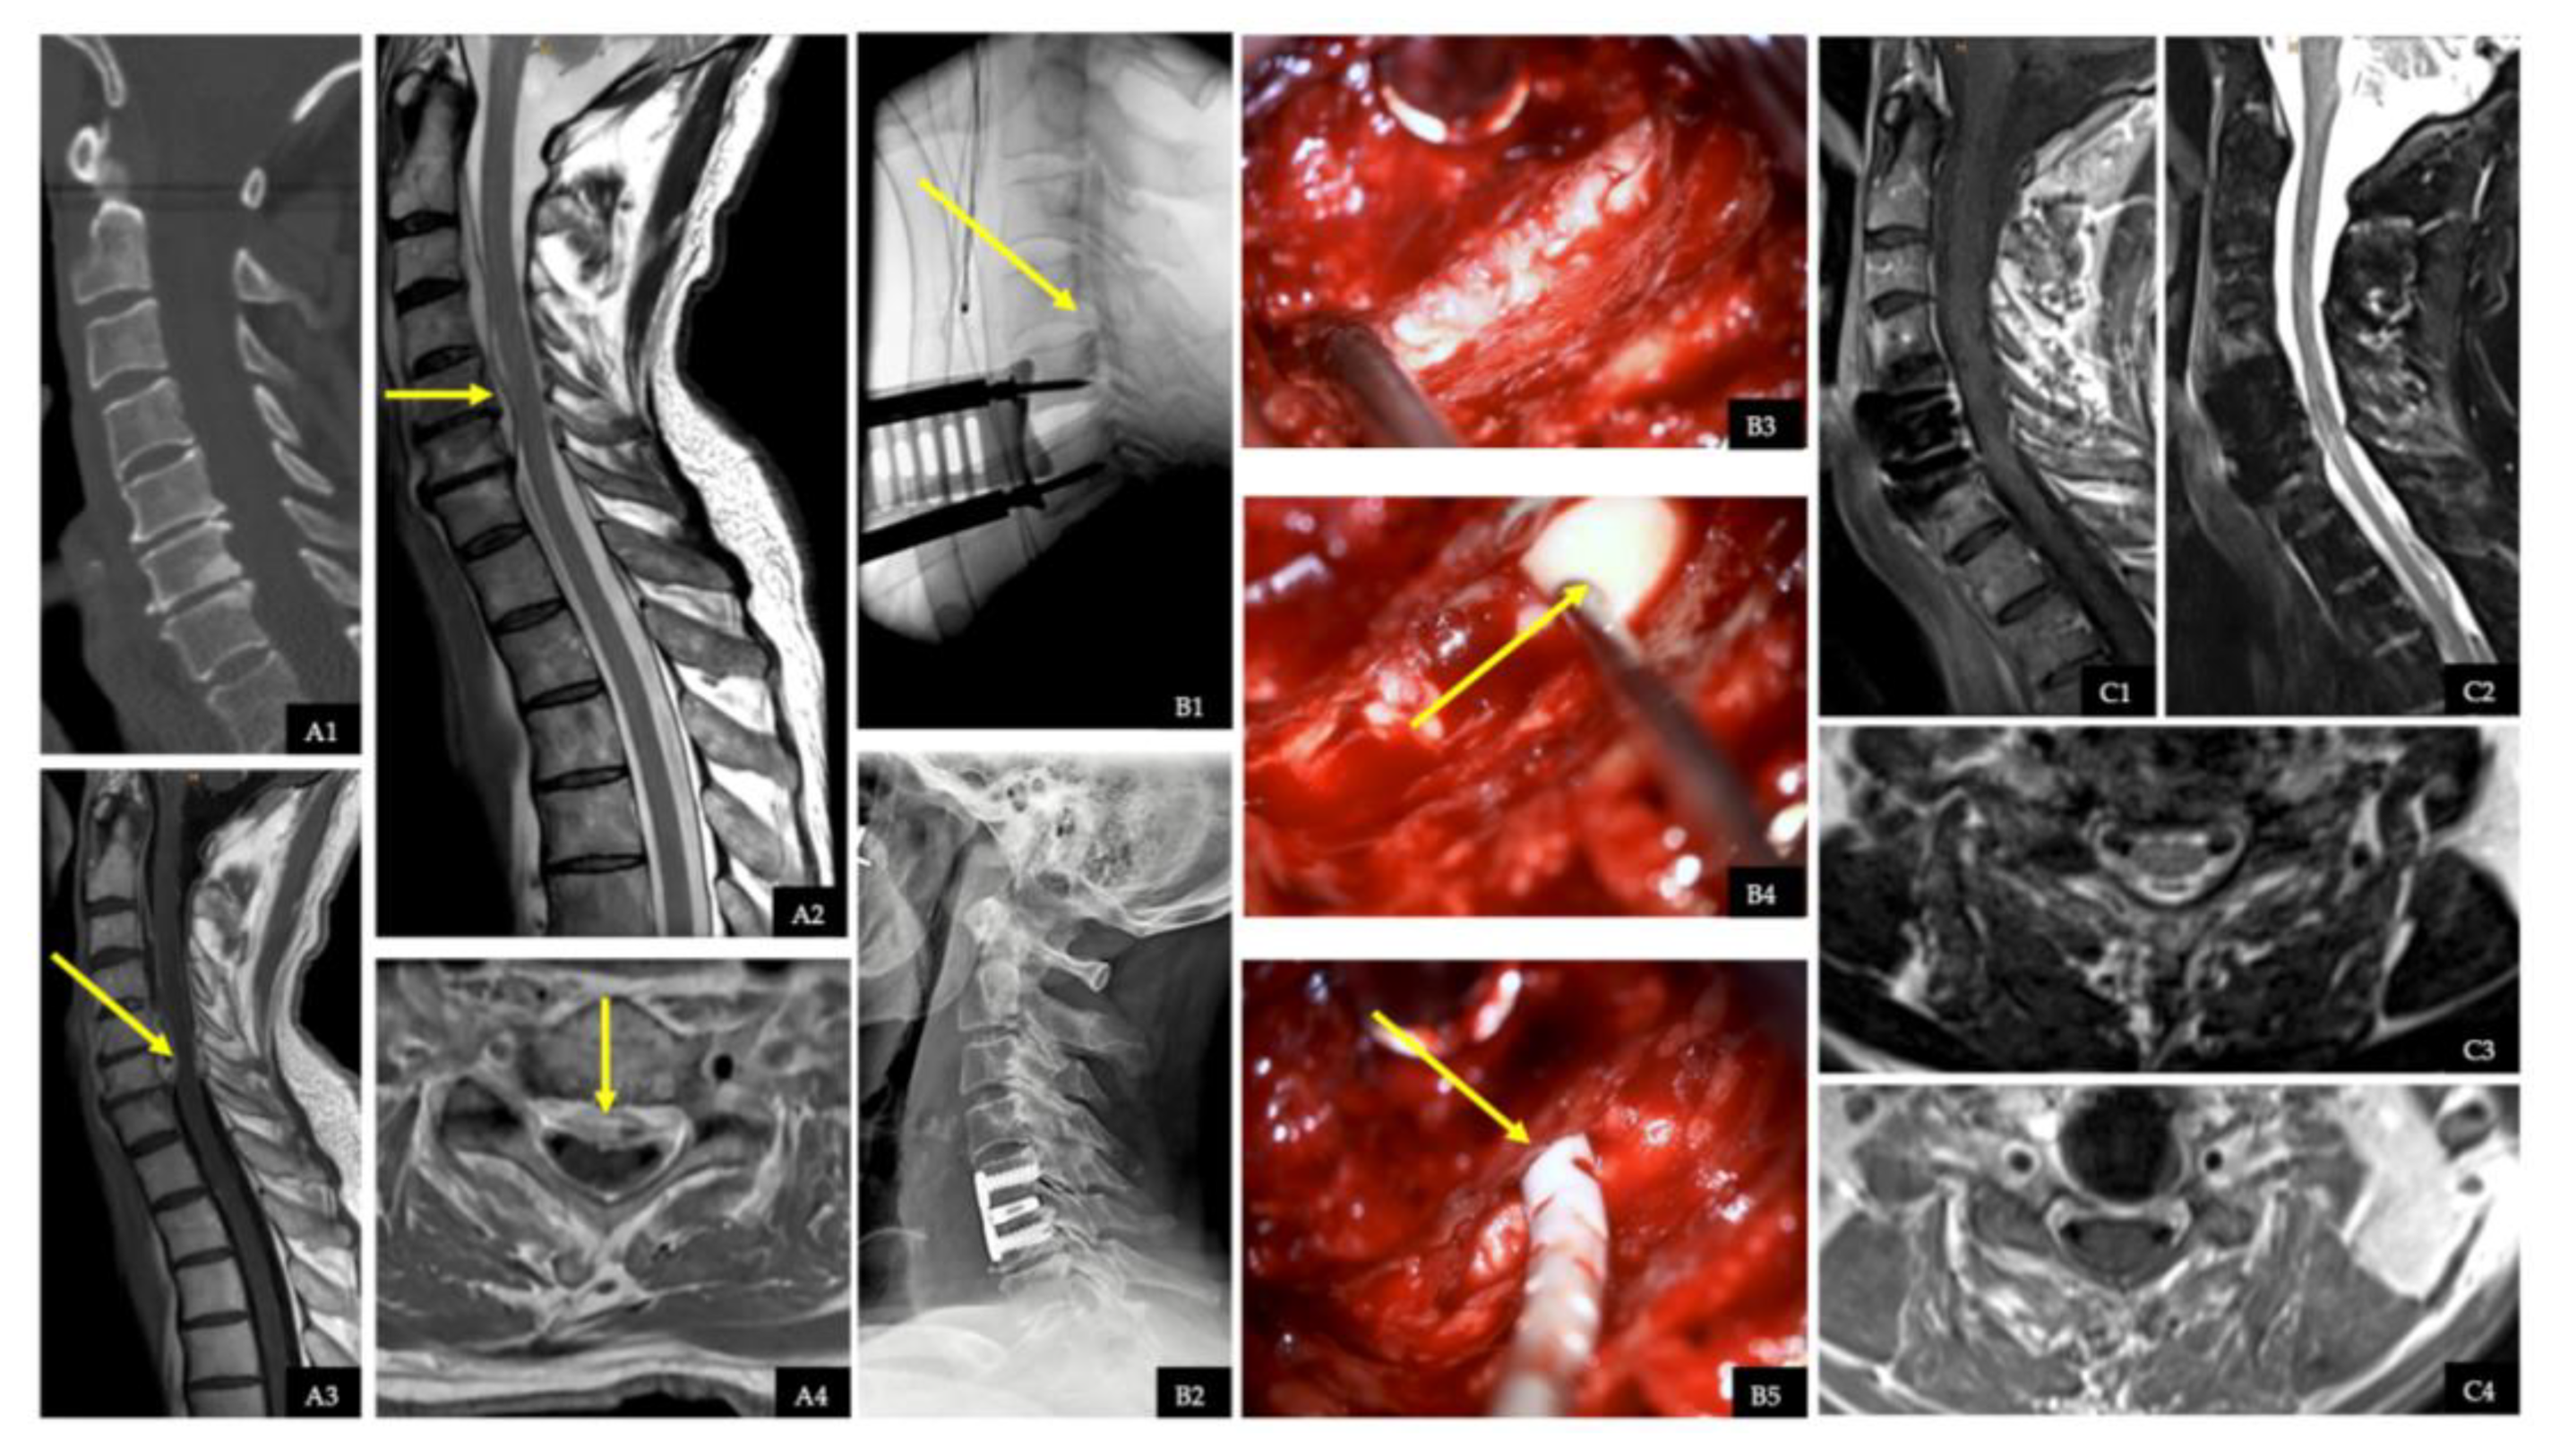

2.5. Illustrative Case with Spinal Epidural Abscess